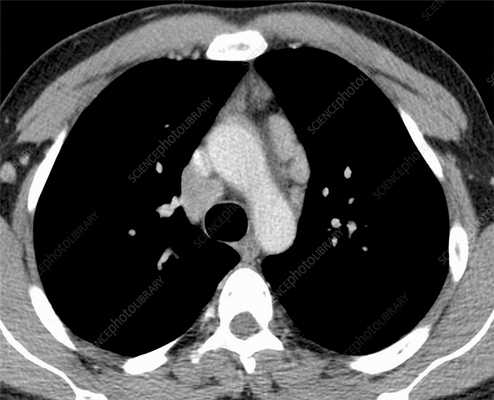

Лимфомы медиастинальной локализации не всегда диагностируются при рентгенологическом обследовании. Компьютерная томография, более детально, чем обзорная рентгенография позволяет рассмотреть конгломерат опухоли, увеличение лимфоузлов средостения, вовлечение паратрахеальных, трахеобронхиальных, прикорневых лимфатических узлов. Диагностическая значимость магнитно-резонансной томографии в верификации лимфом средостения признается не всеми авторами.

КТ ОГК. Объемное образование в средостении (патологически измененный лимфоузел), подтвержденная лимфома.